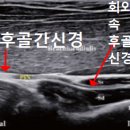

• 요골 | 홍콩여행가서 요골신경마비 걸린 사람의 후기

에스컬레이터가 있고 건물 내부가 넓지 않아 접근하기 편했음! ​ ​ 주의. 요골신경마비 검사할 땐 하루 일정을 그냥 비워두는 편이 좋습니다 ​ 10시 10분 내원 후...덕분에 다이아를 찍었습니다 우와 ㅋㅋ 자랑이당! ​ ​ 초음파 검사 후기 초음파 검사해주신 의사 선생님 존함은 기억 안 나지만 정말 친절하시고 꼼꼼하게 잘...

레츠 자서전(2025-10-12 23:34:00)